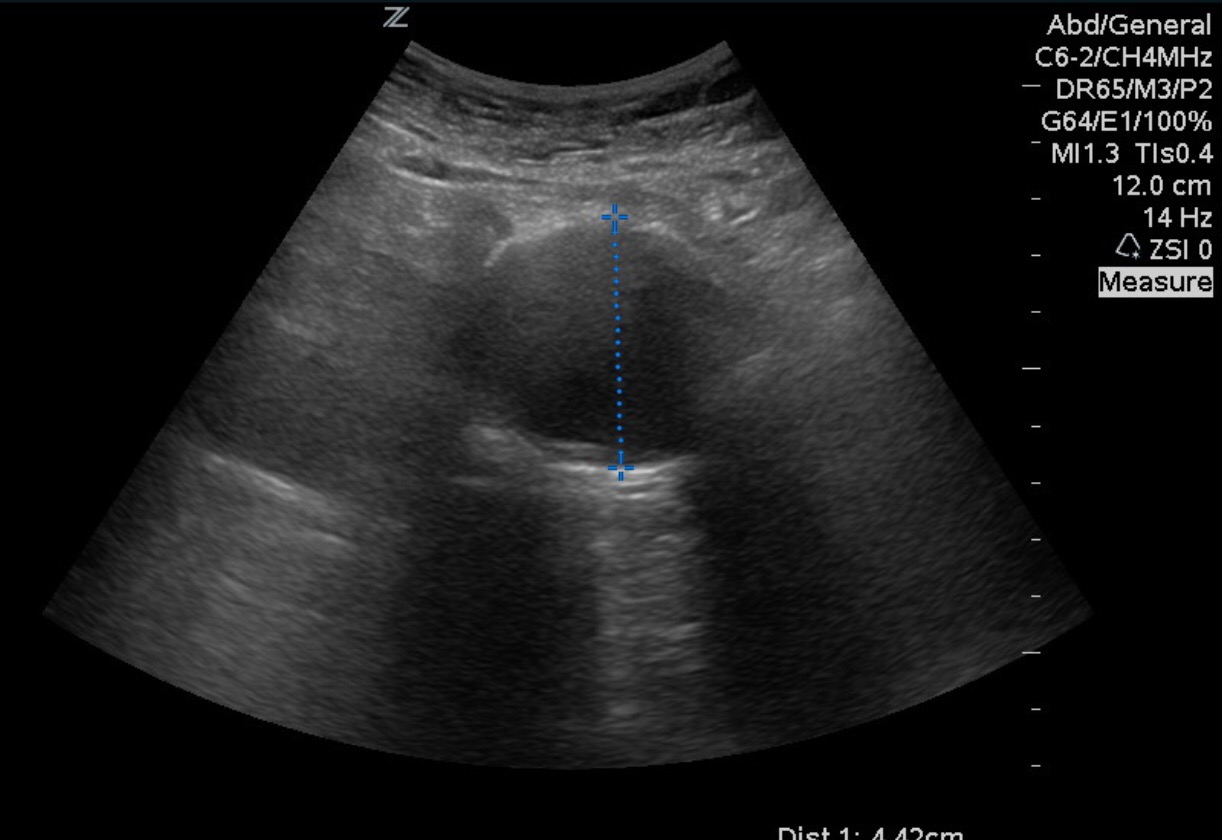

When measuring the abdominal aorta you need anterior to posterior OUTER diameter. Not inner diameter. This was large enough it didn’t matter.